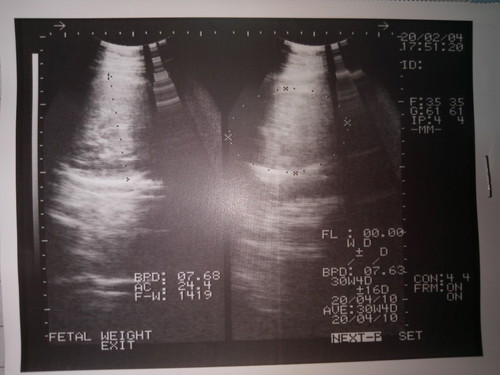

ดูเพศจะต้องเห็นเป็นรูปร่างค่ะแม่ แต่แบบนี้หมอซาวธรรมดาค่ะ ถ้าหมอนัดอัลตร้าซาวด์เมื่อใหร่ถึงจะเป็นการ ซาวเห็นเพศค่ะ

เห็นแต่หัวค่ะ ถ้าให้แต่รูปหัวมาแม่ก็คงต้องถามหมอเอานะคะคงตอบอะไรไม่ได้

ต้องดูตรงหว่างขาค่ะแม่ ถ้าไม่จู๋แหลมๆ ก็ลูกสาว บ้านนี้ได้ลูกสาวค่ะ

ใบซาว์ดใบนี้ไม่สามารถดูเพศได้ค่ะ

ภาพนี้ไม่มีอะไรบ่งบอกเลยคะ

ใบซาวเป็นส่วนหัวค่ะ